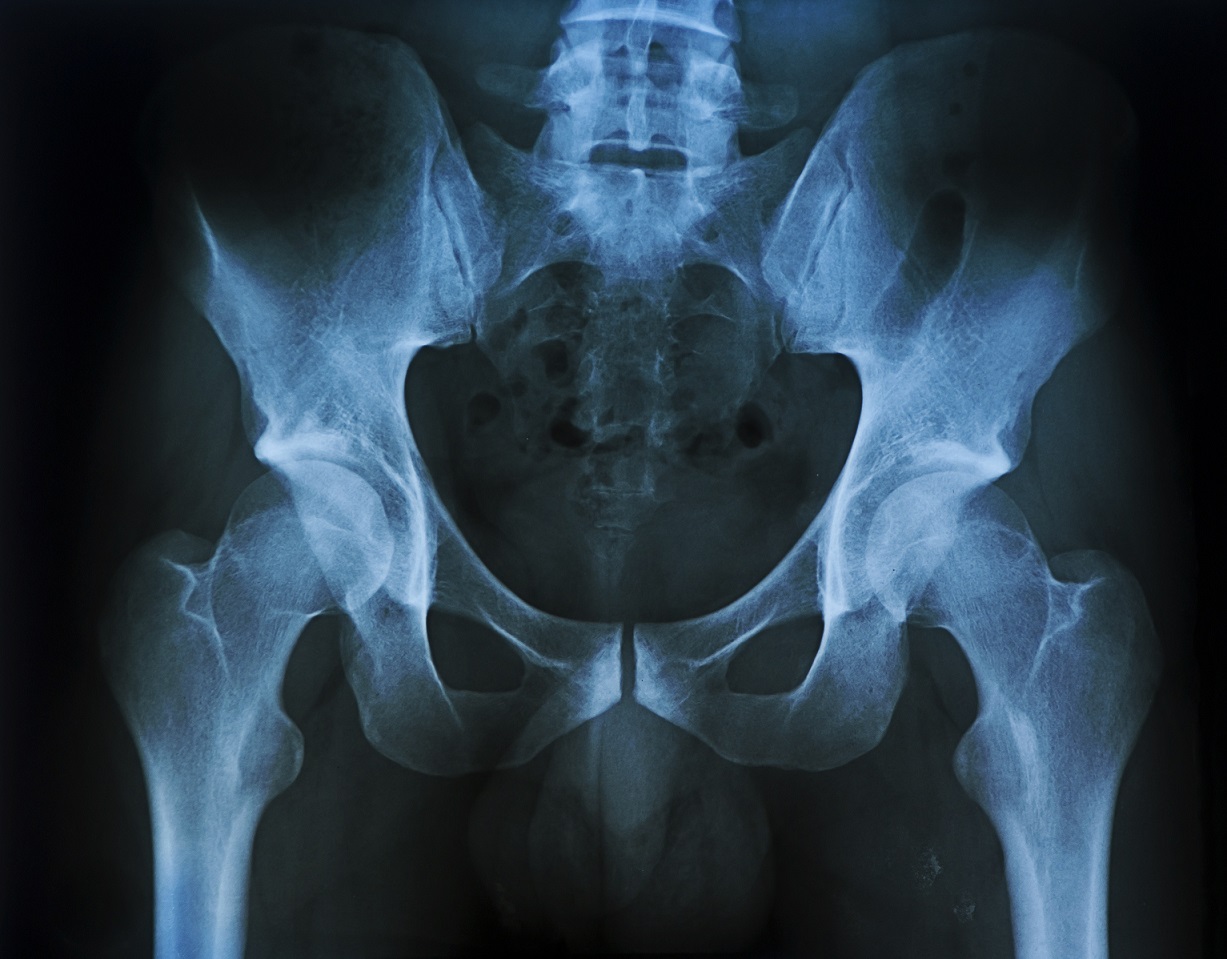

Реабилитация после перелома крестца и лонной кости в Славянске-на-Кубани

Качественная реабилитация после перелома крестца и лонной кости в Славянске-на-Кубани по недорогой стоимости проводится командой дипломированных специалистов частного центра восстановления «Исток» с заботой о каждом пациенте и применением персонального подхода. Такая травма заднего отдела тазового кольца довольно серьёзная и может привести к тяжёлым и необратимым последствиям для жизни и здоровья человека.